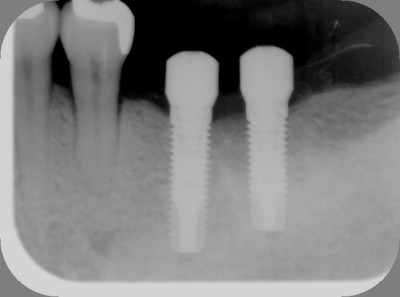

インプラントの術前・術後 Kさん